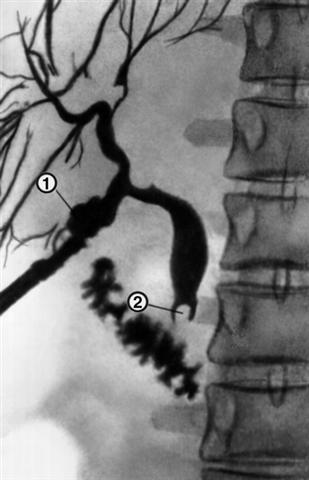

Рис. 1. Фистулограмма неполного наружного желчного свища: 1 — свищевой канал, контрастированный через дренажную трубку; 2 — камень в общем желчном протоке.